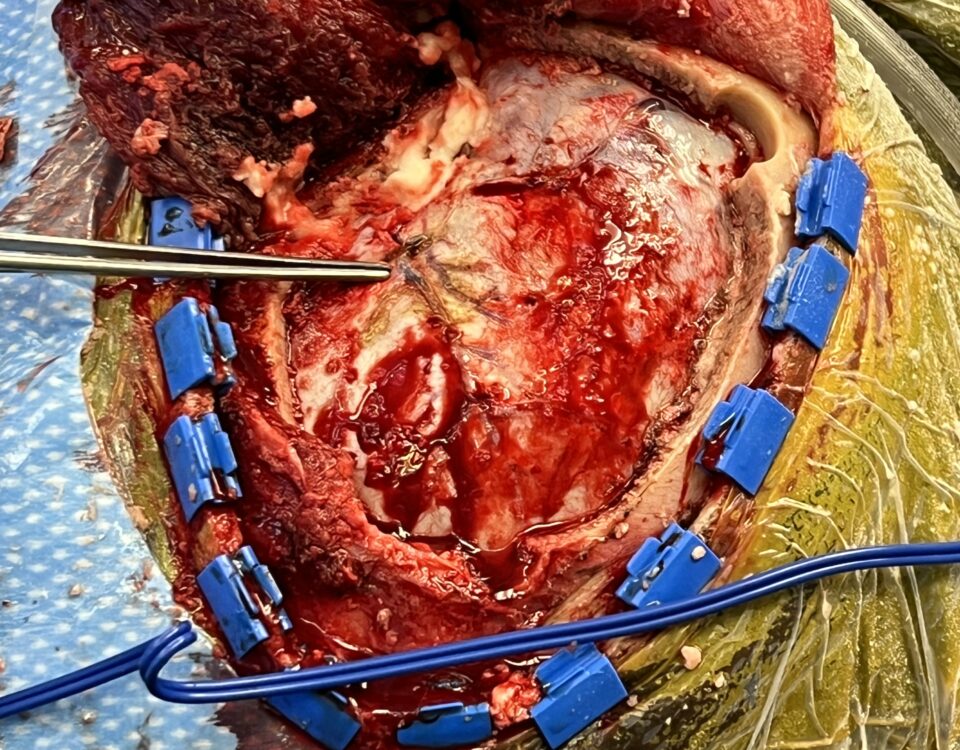

July 21, 2022

This 62-year-old female presents with chronic intractable low back pain with radiation down the front of her thighs. The patient had had two prior fusion surgeries: […]